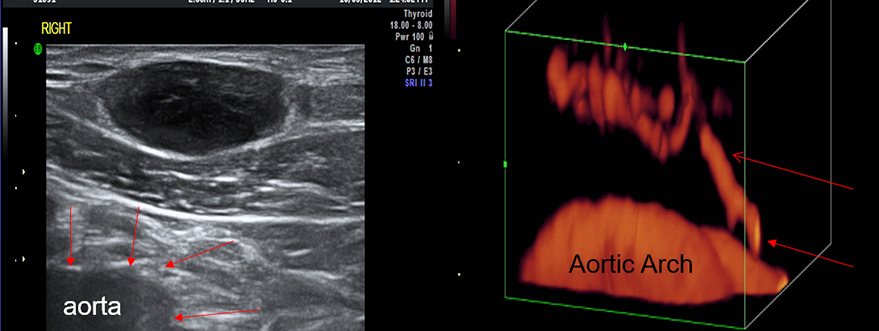

VASCULAR LESION PATIENT ON BIOLOGICS

CLINICAL EXAM = LIPOMA SUBCLAVICULAR LOCATION

PATHOLOGY=FOLLICULAR LYMPHOMA “FLORID TYPE”

NOTE: VASCULAR CONNECTING VESSEL FROM SUBCLAVIAN ARTERY

Not all metastases are clinically hard. This patient was referred for a probable fatty tumor at the clavicle. When we did the imaging of the upper oval black area, it was not clearly demonstrated as an intact border. The Doppler shows vessels that are going into it. Fatty tumors or benign tumors do not have tumor vessels. In this case, we see the vascular supply to the tumor connected to the great vessels in the chest wall. A biopsy of this tumor might have punctured a major vessel causing blood loss on further complications.